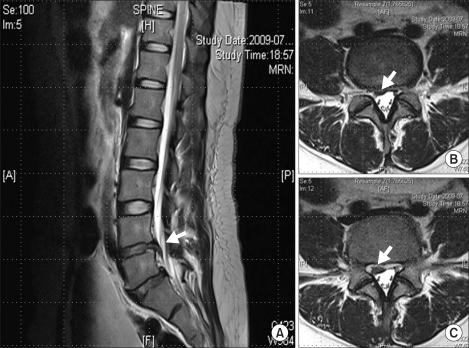

Spinal nerve root swelling mimicking intervertebral disc herniation in magnetic resonance imaging -a case report-.

A herniated intervertebral disc is the most common type of soft tissue mass lesion within the lumbar spinal canal. Magnetic resonance imaging (MRI) is a useful tool for the assessment of patients with lower back pain and radiating pain, especially intervertebral disc herniation. MRI findings of intervertebral disc herniation are typical. However, from time to time, despite an apparently classic history and typical MRI findings suggestive of disc herniation, surgical exploration fails to reveal any lesion of an intervertebral disc. Our patient underwent lumbar disc surgery with the preoperative diagnosis of lumbar disc herniation; however, nothing could be found during the surgical procedure, except a swollen nerve root.

椎间盘突出是腰椎管内最常见的软组织肿块病变类型。磁共振成像(MRI)是评估腰痛和放射性疼痛患者的有用工具,尤其是椎间盘突出症。椎间盘突出症的 MRI 表现具有典型特征。然而,有时尽管有明显的典型病史和提示椎间盘突出的 MRI 表现,但手术探查未能发现任何椎间盘病变。我们的患者接受了腰椎间盘手术,术前诊断为腰椎间盘突出症;然而,手术过程中除了神经根肿胀外,什么也没有发现。